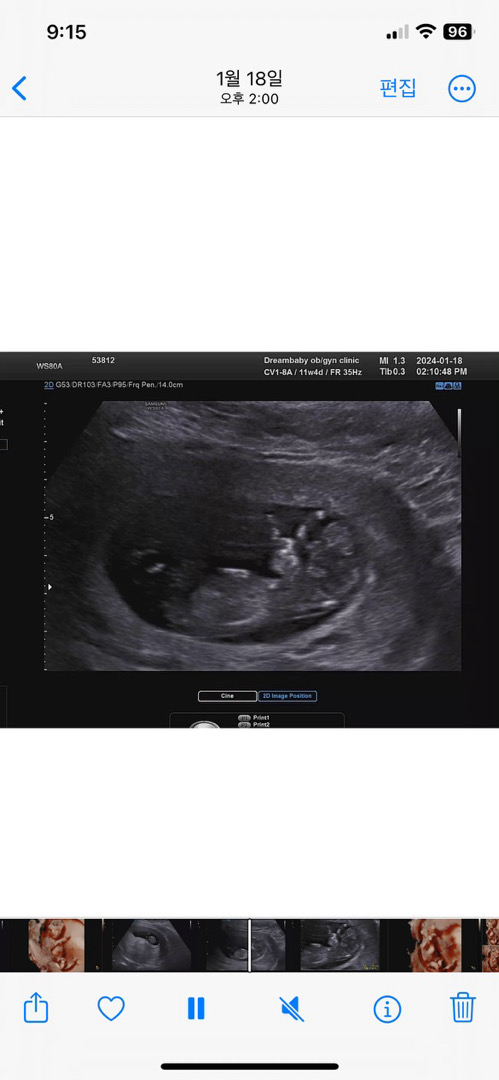

12주 각도법 성별 알수있을까요?

산부인과에서는 말씀을 안해주시더라구요 각도법 고수분들의 조언을 구합니다!

사진이 흐리고 애매해서 아닐수도있는데 아들같아보여요~

그렇군요 그나마 각도법에 적용할수 있는 모습이 이것뿐이네요..ㅠ